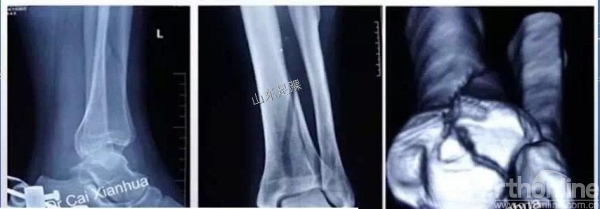

(2)一期:(恢复肢体长度和力线)跟骨牵引;外固定;腓骨骨折复位内固定、胫骨后踝骨折有限切开复位内固定;预防血栓。

(3)二期:约10—14天后,胫骨骨折切开复位内固定。

复位胫骨远端关节面时,需要辨认3个主要的骨折块:Volkmann骨块、Chaput骨块和内踝骨块。

关节面复位要由后向前、由外向内的顺序进行,后方的Volkmann骨块是复位的关键。

3.术前CT评估关节面粉碎程度